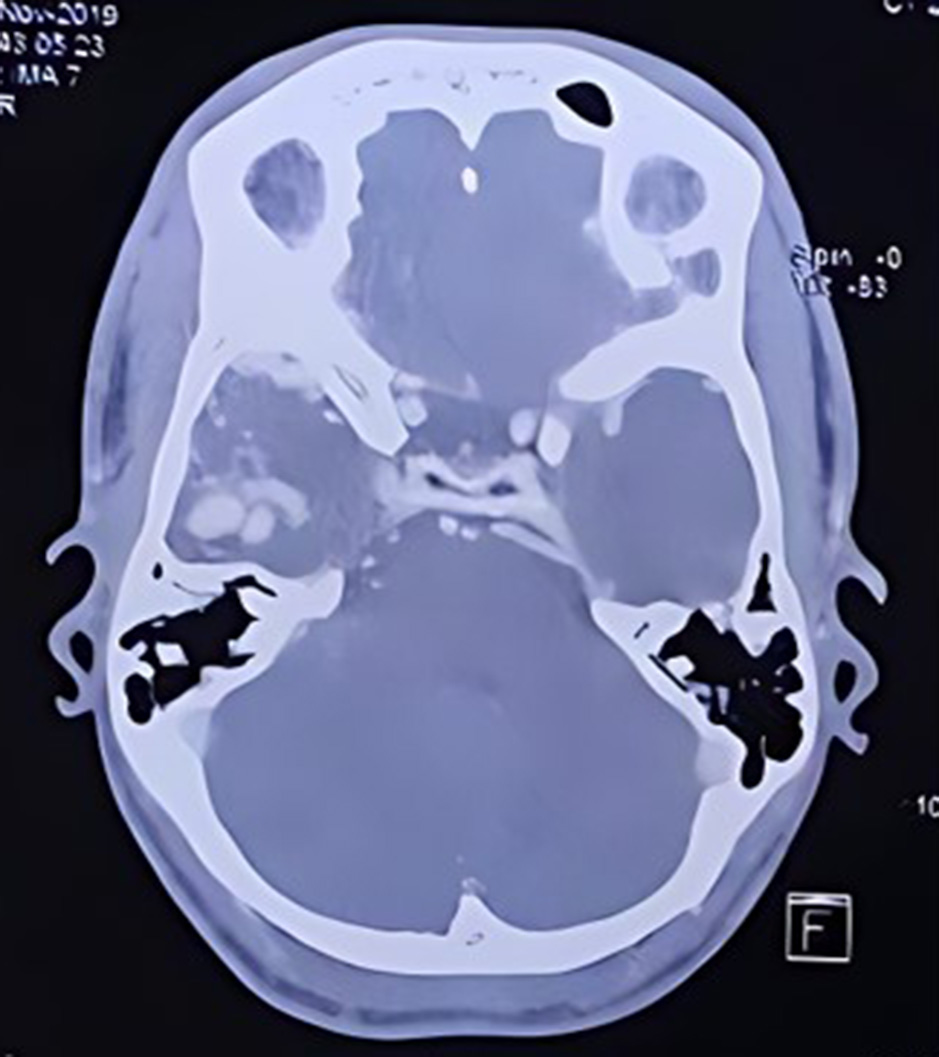

Fig. 2, 3, 4, 5 are the representative images of the patients, showing the AVM, its localisation and planning for purely descriptive purpose only.

Fig. 2. CT angiogram cerebral vessels showing AVM in the Right temporal region